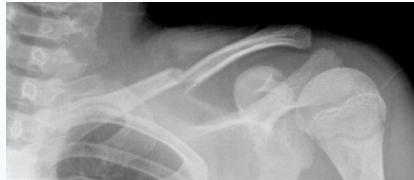

- Birth injury

- Fall on outstretched hand

- Heals well conservatively

- Sling or figure-of-8 bandage (better)

Note: If the mother comes with swelling, assure her that it’s Callus - no need for follow up.